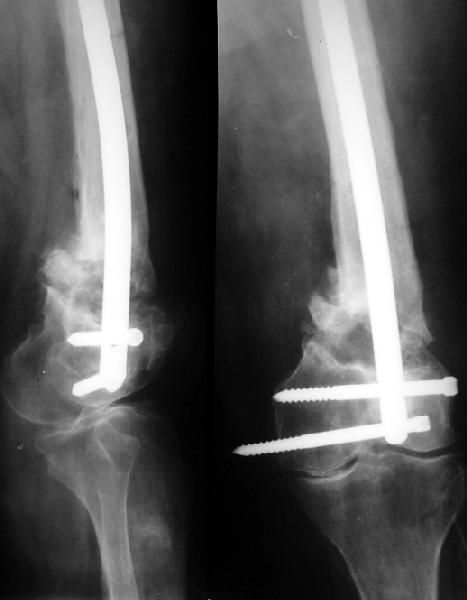

Здесь вполне можно не вмешиваться открыто. Сделать fixator-assisted nailing. Все закрыто убрать. Хорошо восстановить ось. Через медуллярный канал ручными развертками освежить концы отломков. И заштифтовать. Раз уже был ретроградный стержень - то ретроградно. Я бы взял большеберцовый гвоздь, чтобы ввести винты в разных плоскостях. Ну и гвоздь потолще, и винты 6 мм.

Вот давний пример похожего ложного сустава после неоднократных остеосинтезов.

Александр здравствуйте! Вы представили очень интересный случай, отличный рентгенологический и функциональный результат. Меня смущает только достаточно выраженный гонартроз, как в случае с Вашей пациенткой так и с моей.

Отправитель: Alexander Chelnokov 02 Сентябрь 2017, 19:43

Функциональный результат не очень, у пациентки перед нашим остеосинтезом уже не было движений в колене. По крайней мере, в ближайшие годы она была счастлива, что у нее нога опорная стала, и не надо ни костыли, ни ортез, ни компенсацию длины